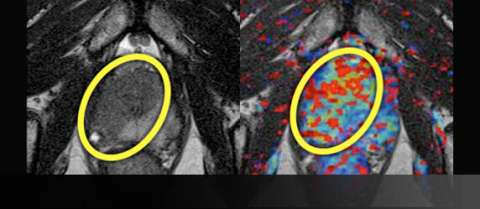

LEFT: T2-weighted image prior to treatment shows large, low-signal mass (yellow oval) on the right crossing midline anteriorly

RIGHT: Color perfusion map shows correspondingly increased perfusion (yellow-green pixels) with washout (red pixels)